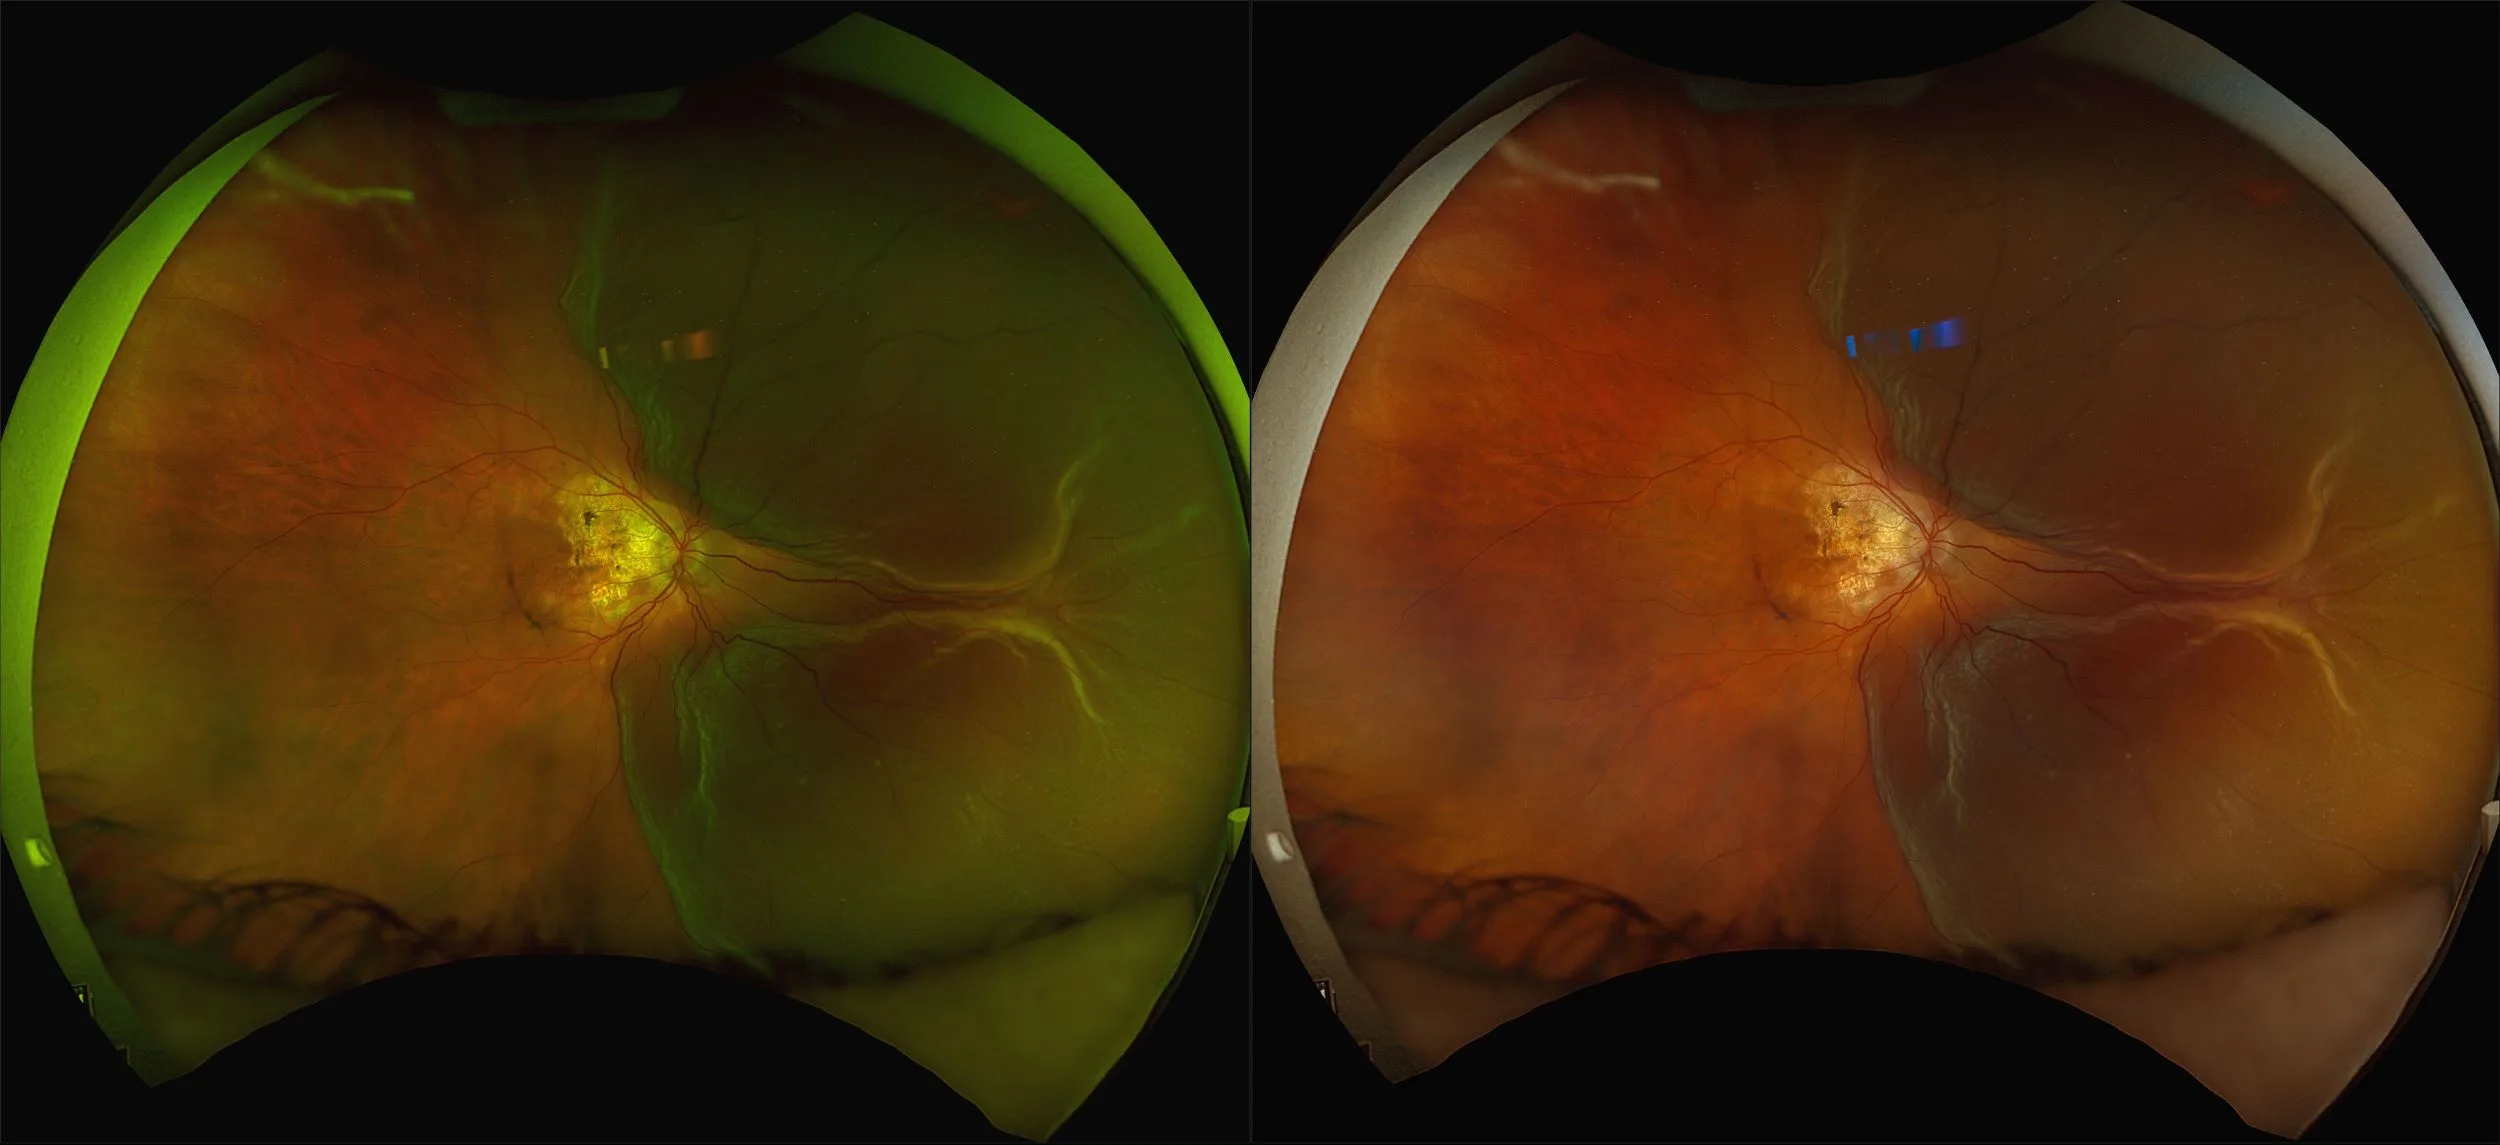

MonacoPro - Retinal Detachment, RG, AF, OCT

A retinal detachment (RD) is the separation of the sensory retina from the Retinal Pigment Epithelium (RPE) (outer segments of the photoreceptors from the microvilli of the RPE).